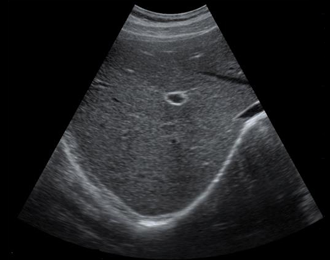

临床图像